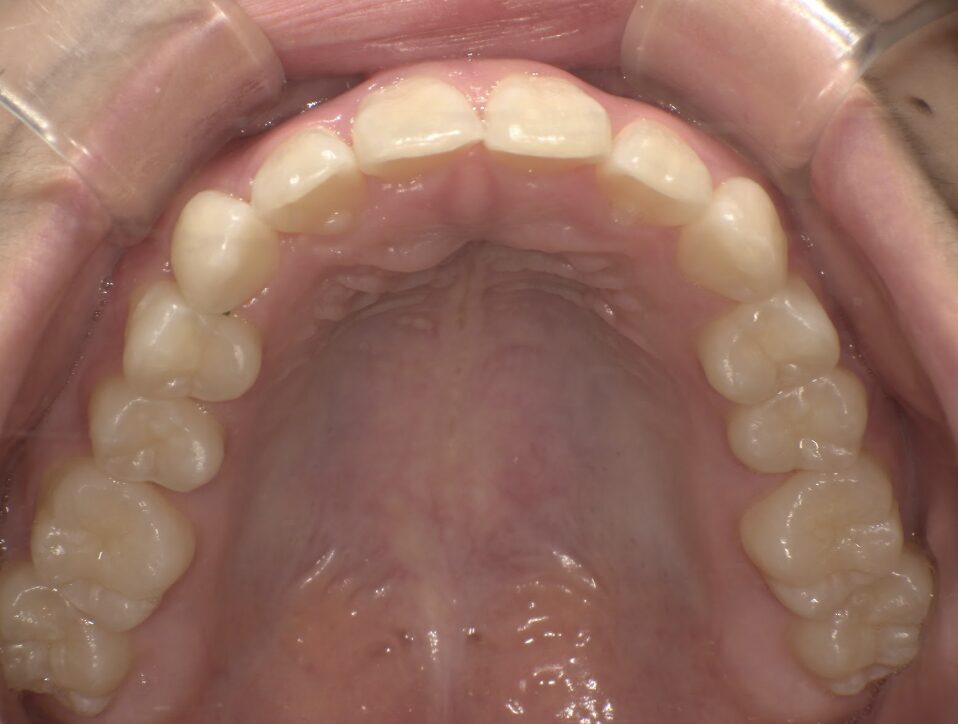

クロスバイト

治療前

ガタガタを主訴に当院を受診され、右上2番にクロスバイトを認めました。IPRを使用してマウスピース型矯正装置(インビザライン)を使用し改善を行いました。